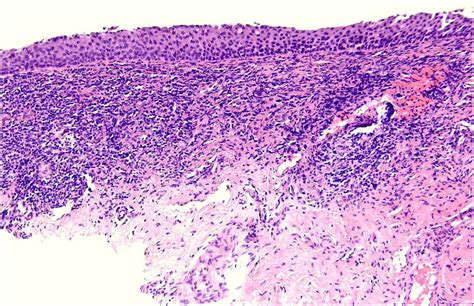

At its core, Erosive Lichen Planus is an autoimmune inflammatory condition. While the exact cause remains unknown, it occurs when the body's immune system mistakenly attacks the lining cells of the mucous membranes. This persistent inflammation leads to the breakdown of the tissue, resulting in painful, red, and eroded areas that are often rimmed with white, radiating lines known as Wickham striae. Because it is a chronic condition, patients often experience periods of remission followed by painful flares.

Identifying the condition early is vital, as the chronic inflammation and constant cell turnover associated with this form have been linked, in rare instances, to an increased risk of oral cancer. Therefore, consistent monitoring by a dental professional or an oral medicine specialist is non-negotiable for those diagnosed with the condition.